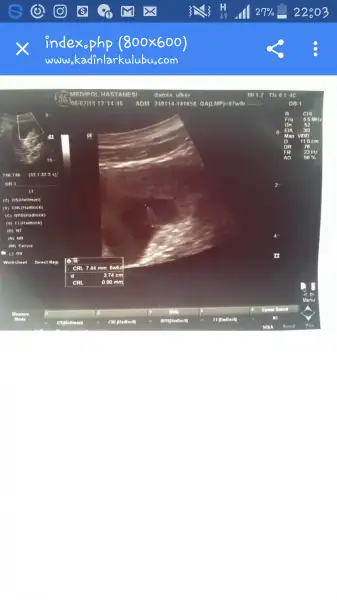

Yeşim bak bu dünku ultrasonum ve geçen hafta ki ultrasonum. Geçen hafta ki 8mm miş bu hafta ki 1.5 cm çıkmış.

Eklentiler

• 2016-10-06 12.58.20.webp

2016-10-06 12.58.20.webp

12 KB · Görüntüleme: 82

Bir de ilayi ilk gördüğüm ultrasonu buldum kadınlar kulübünde. Sanırım ilk 3.5 cm iken görmüşüz ilayi. 6+5 günlükmüş o zaman yavrum. Ama kesenin boyu mu yoksa ilayin boyumu 3.5 cm onu anlamadım. Karşılaştırma yapmak istedim yapamadım da

• Screenshot_2016-10-05-22-03-51.webp

Screenshot_2016-10-05-22-03-51.webp

9 KB · Görüntüleme: 68

Tam okuyamadim ama bebek CRL , kese de GS yazmasi laziim